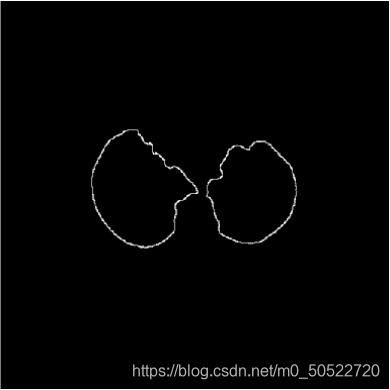

(7)肺质边缘提取——sobel算子

利用sobel算子将上图肺质的边缘提取出来,方便我们观察肺质的形状。